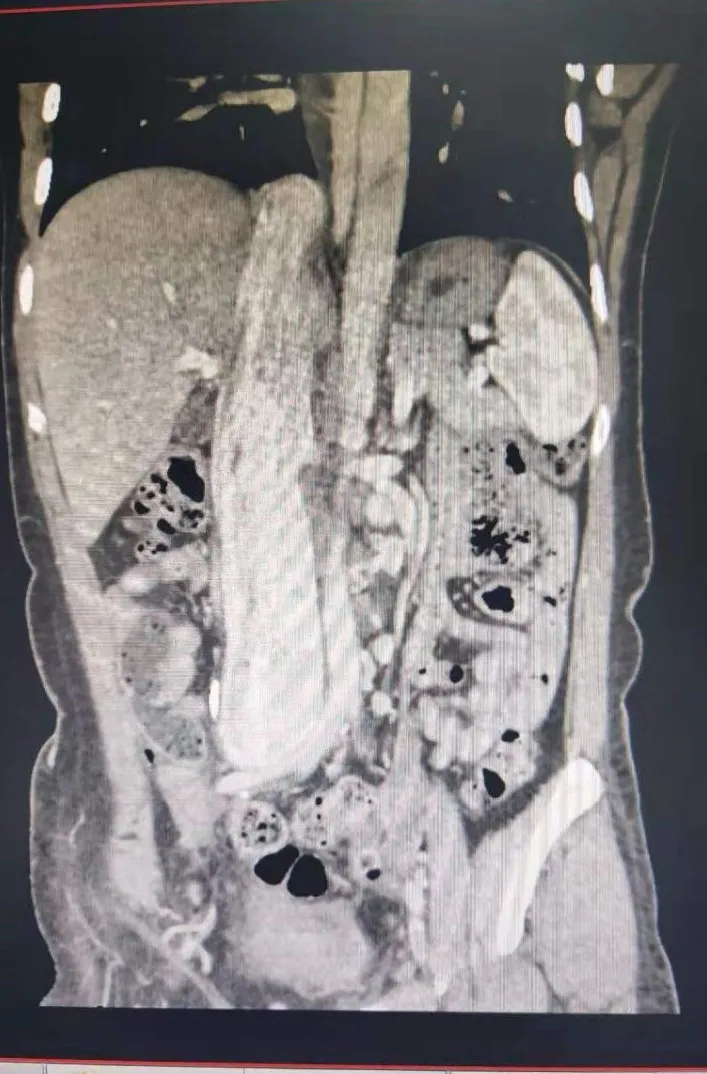

“这个肿瘤非常特殊,它从下往上逆行生长,一直长到了病人心脏里面。”凭着外科医生的敏感直觉,有着二十多年丰富临床经验的孙玉桂副教授第一时间发现了这个“不速之客”的特殊之处:狡猾的肿瘤不但躲在大血管里面,还变成了两个分支进行躲藏,一支藏到了肝脏附近,另外一支则藏进了心脏里面,类似一个“Y”型的形态。由于肿瘤从病人大腿根部一直长到了心房位置,最粗的地方有鸡蛋大小,肿瘤不但体积大、长度长,而且离人体许多重要内脏器官的位置都很靠近,手术当中稍有不慎,后果不堪设想。

怎么才能既保证完整切除肿瘤,又不过度骚扰损伤周围器官?孙玉桂副教授立刻与张立飞教授,展宇飞、肖智宏医师等进行了严谨的讨论:肿瘤从盆腔的右侧髂内静脉作为起始部,到达髂总静脉后就发出两个分支,一支沿着下腔静脉逆行到了肝脏门静脉附近,另一支则沿着下腔静脉逆行向上直接长到了右心房里面,因为下腔静脉是人体下半身所有器官的血液回流必经之路,肿瘤沿着下腔静脉管内生长,血供又比较丰富,如果要行手术切除,将是一个极大的挑战——既要从髂内静脉找出肿瘤的“头部”,还要打开心脏找到肿瘤的一个“尾巴”,并找到肝脏门静脉的另一个“尾巴”,这个过程中要保证肿瘤完整切除,不能撕裂扯断,不能破坏下腔静脉正常形态,不能影响各个器官的正常血液回流,这需要体外循环下保证患者正常体循环供血的前提。不仅需要心脏外科、血管外科、胸外科的专业手术技术,还需要多个外科手术科室的紧密配合、协同支持。

术前术后下腔静脉对比: